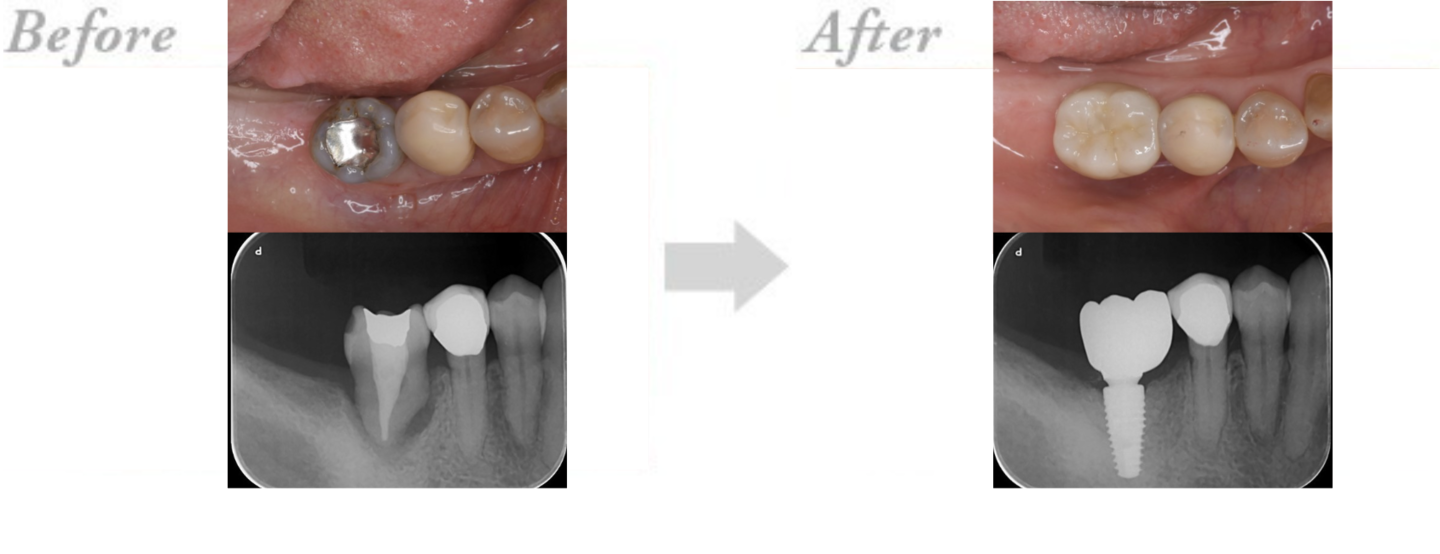

◆インプラント治療の実例 CASE1